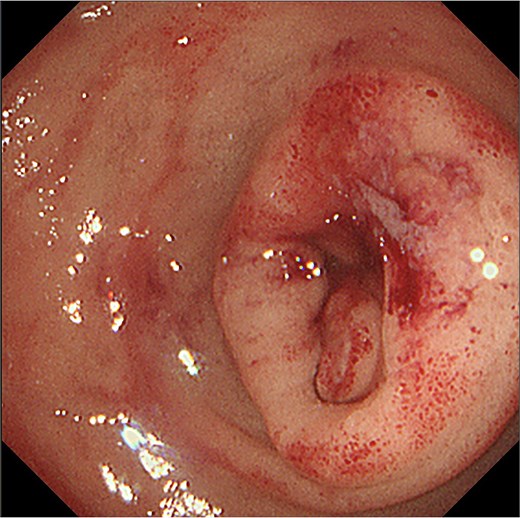

A 70-year-old male who worked as a farmer following retirement from office-work was referred to our hospital with anorexia, nausea, and abdominal pain. The patient had a history of hypertension, diabetes mellitus, gastroesophageal reflux disease, and benign prostatic hyperplasia. He had not smoked for 10 years and consumed one glass of the alcoholic beverage shochu daily. Contrast-enhanced computed tomography (CT) of the abdomen revealed peritonitis/duodenal perforation and a 4 cm duodenal tumor in the 1st and 2nd duodenum portions, respectively (Fig. 1a–c). Emergency laparotomy was performed to close the perforation. Gastroduodenal endoscopy revealed duodenal stenosis with a tumor in the 2nd portion (Fig. 2). Biopsy indicated a poorly differentiated adenocarcinoma; however, magnetic resonance imaging (MRI) showed no stenosis in the bile or pancreatic ducts (Fig. 3a and b). Preoperative laboratory data revealed normal levels of the tumor markers carcinoembryonic antigen (CEA) 1.5 (<5.0) and CA19–9 12.6 (<37.0).

Gastro-duodenal endoscopy. Gastro-duodenal endoscopy revealed duodenal stenosis with the duodenal tumor in the 2nd portion. The tumor was biopsied, with subsequent analysis revealing adenocarcinoma.